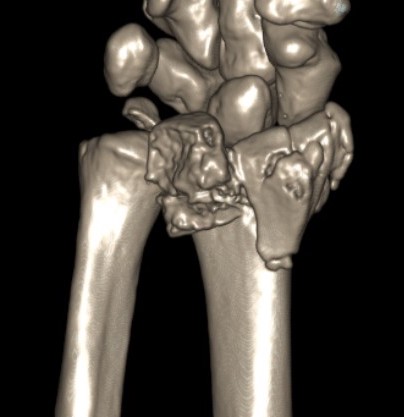

Dorsal distraction plating

Indication

Internal radiocarpal distraction

- unreconstructable distal radius fractures

- early weight bearing in poly trauma patients

- osteoporotic bone

Advantage - no pin site infection from external fixation

Disadvantage - need to remove plate at 3 - 4 months once fracture united

Results

- systematic review of dorsal distraction plating

- 50% of wrist flexion extension compared to contralateral limb

- grip strength 80%